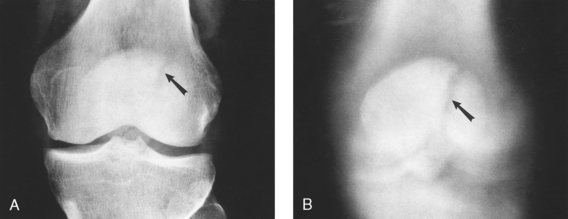

Fig. 6-156 A, Normal tangential radiograph of congruent patellofemoral joints, showing patellae to be well centered with normal trabecular pattern. B, Abnormal tangential radiograph showing abnormally shallow intercondylar sulci, misshapen and laterally subluxated patellae, and incongruent patellofemoral joints (left worse than right). (Courtesy Alan J. Merchant.)